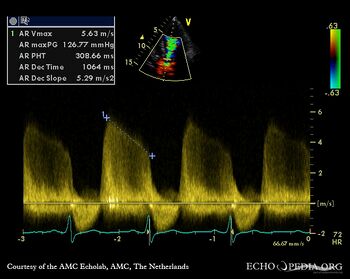

E00448.jpg

Continuous-wave signal of severe aortic regurgitation Pulsed-wave doppler from abdominal aorta, diastolic flow reversal